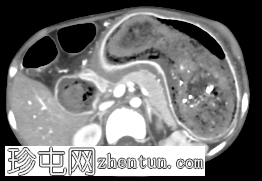

冠状位增强扫描(门静脉期)

胃腔内可见巨大肿块,内含斑驳状软组织、气体和高密度灶,延伸至幽门、十二指肠和近端空肠(长发公主综合征)。十二指肠轻度扩张。

胃壁强化减弱及胃壁积气区域。